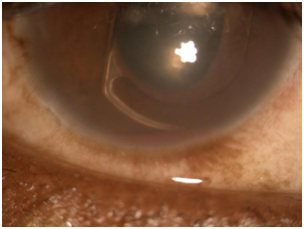

Patient presented in urgent care reporting that the condition is not any better with complaints of pain, redness, photophobia, tearing, discharge, discomfort, and shortness of breath. Patient reported good compliance on taking prednisolone, Combigan®, Azopt®, but has not obtained atropine from the pharmacy yet. Patients VA was light perception OD and similar entrance testing results as the last follow up. Slit lamp examination revealed microcystic corneal edema, diffuse 3+ PEE, the same anterior chamber findings, except newly noted that the lens OD was a poorly fitting ACIOL touching the cornea and the iris. Intraocular pressures were 47 mmHg, 14 mmHg OD, OS. After dilation, the 2+ vitreous hemorrhage was noted again and all other findings appeared normal (Figures 1−3). Additional diagnostic testing was ordered for exterior/slit lamp photos, which were interpreted as a poorly fitting ACIOL OD with hyphema and NVI. The retinal surgeon performed an intravitreal injection of Avastin® 1.25 mg to regress neovascularization of the iris and to stabilize/improve the eye. Post-injection IOP via tactile measurements were now estimated to be 21 mmHg, 21 mmHg OD, OS. After the injection, the assessment of proliferative diabetic retinopathy with UGH syndrome OD was made. The plan stated to proceed with glaucoma/cataract specialist with ACIOL removal and IOP management.

Figure 1 16x Slit lamp photo of NVI growing over the pupillary ruff.

Figure 2 10x Slit lamp photo of malpositioned ACIOL with haptic rubbing on iris tissue causing hyphema.

Figure 3 16x Slit lamp photo of hyphema with fresh blood inferiorly.